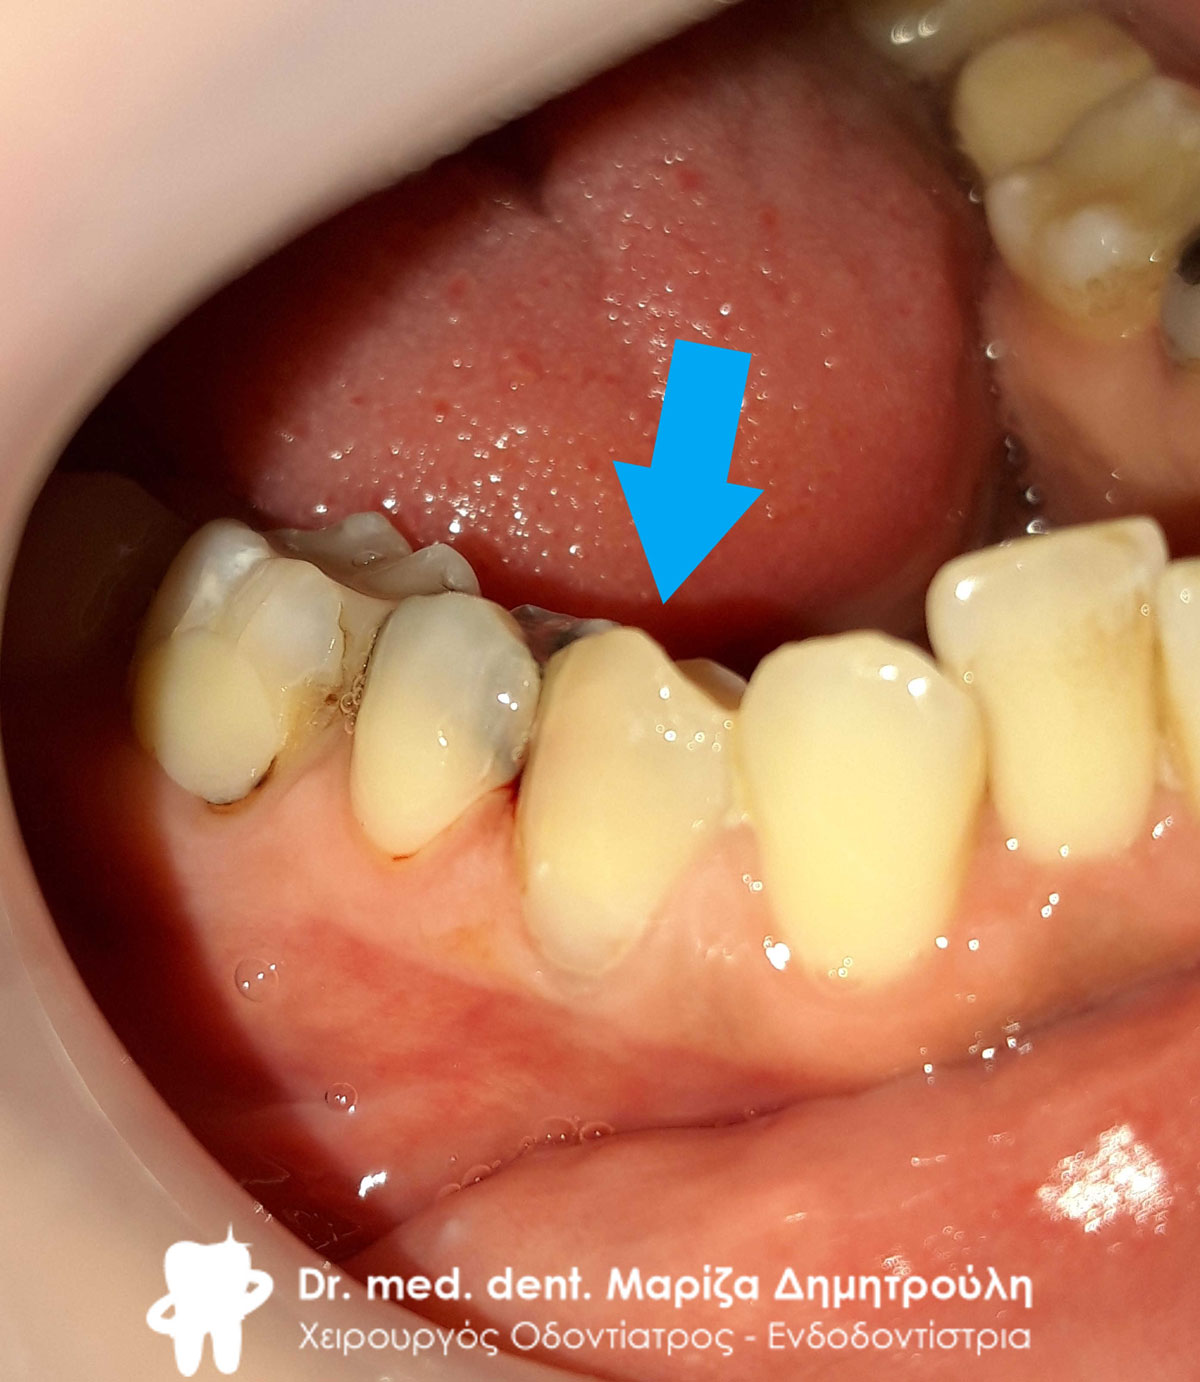

Αρχική κλινική εικόνα της κάτω γνάθου

Εικόνα των τροχισμένων δοντιών με τις απαιτούμενες ανασυστάσεις

Εικόνα των τροχισμένων δοντιών με τις απαιτούμενες ανασυστάσεις

Η ασθενής επιθυμούσε την αποκατάσταση των κάτω πρόσθιων δοντιών, τα οποία είχαν έντονη κινητικότητα. Αναφέρει επίσης οτι την πονάει ο αριστερός κυνόδοντας, ο κάτω δεξιός γομφίος και κάποια άλλα δόντια. Με σκοπό τη δημιουργία μιας άρτιας προσθετικής εργασίας αποφασίστηκε η εξαγωγή των κάτω πρόσθιων δοντιών, τα οποί είχαν έντονη κινητικότητα. Εν συνεχεία απονευρώθηκαν όσα δόντια είχαν έντονο πόνο στην επίκρουση και στο κρύο. Ακολούθως στα δόντια πραγματοποιήθηκε ανασύσταση, τροχίστηκαν και λήφθηκε αποτύπωμα για τον οδοντοτεχνίτη. Κατασκευάστηκε ολοκεραμικό πέταλλο ζιρκονίου, το οποίο συγκολλήθηκε στην κάτω γνάθο.